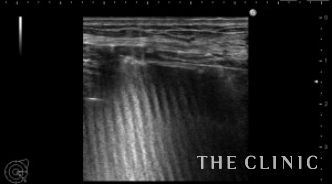

右は穿刺吸引しました。 被膜が残っていますが、ほとんどなくなりました。